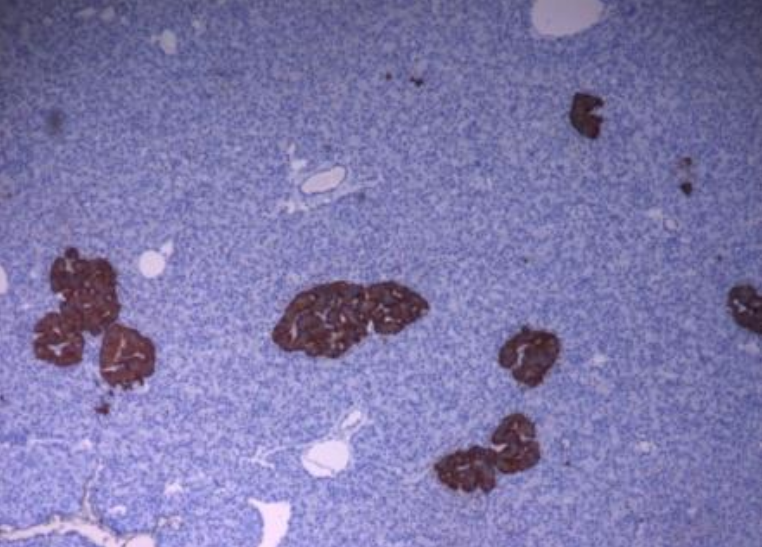

Les îlots de Langerhans ont été mis en évidence par immunohistochimie, à l'aide d'anticorps anti-insuline. Ils apparaissent en marron (coloration à la diaminobenzidine) tandis que les noyaux des cellules exocrines sont contrecolorés à l’hématoxyline (coloration bleue) (×100).

Aujourd’hui, le diabète affecte plus de 420 millions de personnes dans le monde et ce nombre est en constante progression 12. Cette maladie métabolique se caractérise par une hyperglycémie, c’est-à-dire par un taux de sucre dans le sang supérieur à 1,26 g/L à jeun et regroupe plusieurs types de diabète. Les plus connus sont le diabète de type 1 (DT1) ou diabète insulinodépendant et le diabète de type 2 (DT2), anciennement appelé diabète gras. Le diabète de type 1 représente 10 % des cas de diabète et se caractérise par la perte des cellules β qui sécrètent l’insuline, une hormone hypoglycémiante. Ces cellules sont présentes au sein d’amas cellulaires pancréatiques appelés îlots de Langerhans et disséminés dans le tissu exocrine (Figure 1).